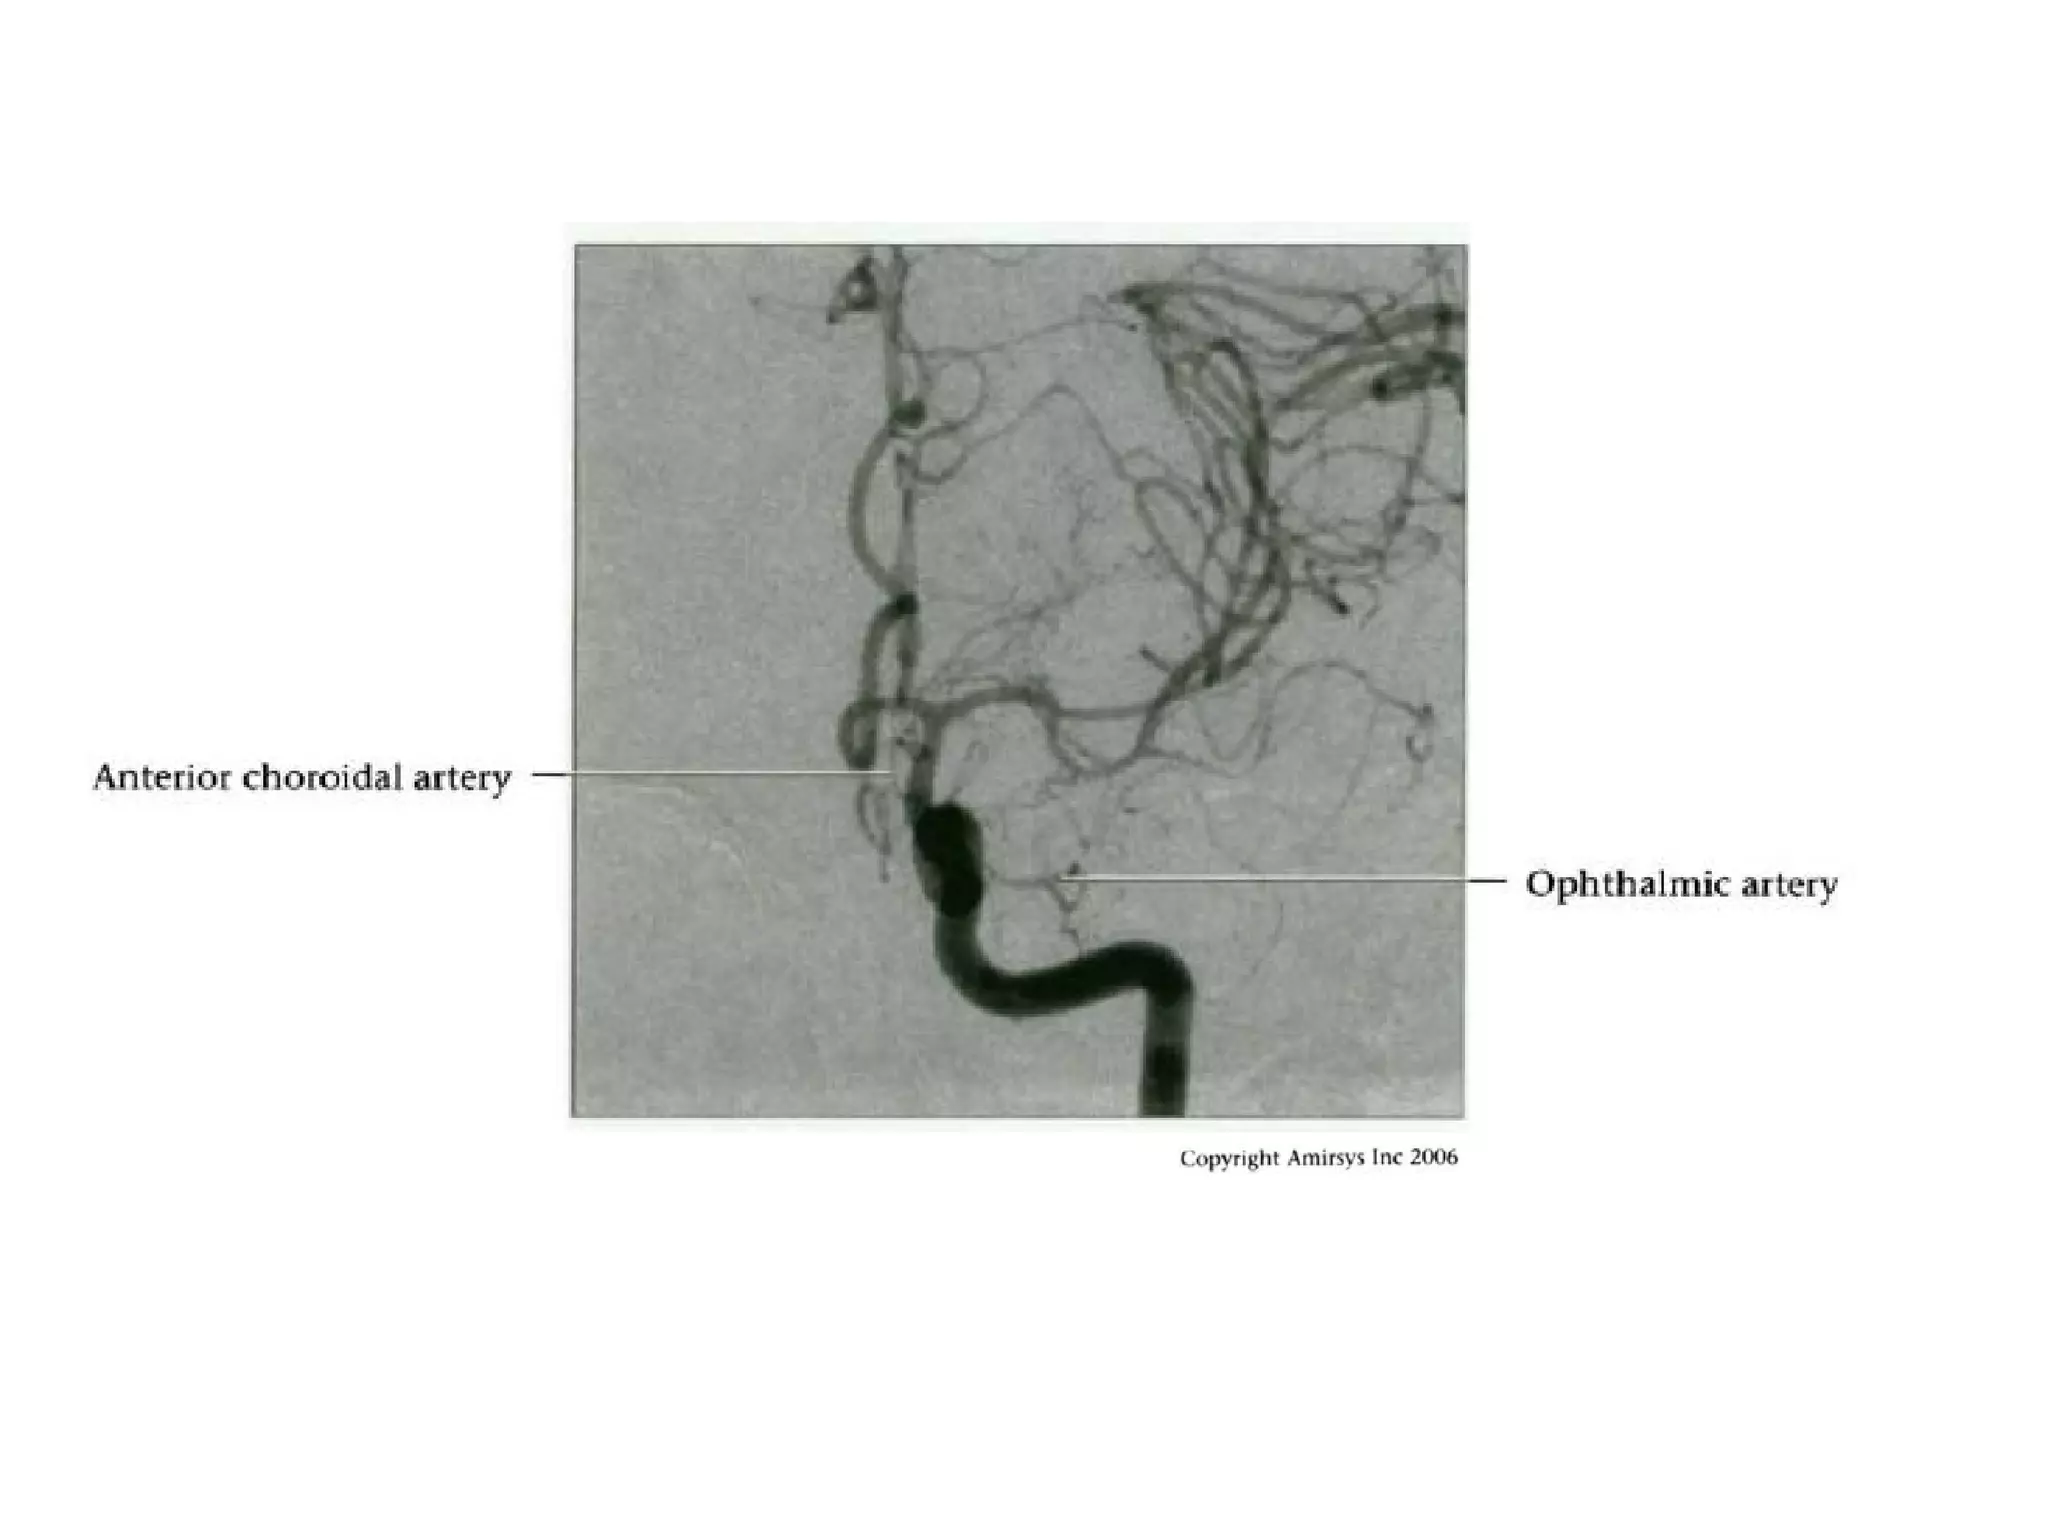

• The anterior choroidal artery, usually a small vessel,

arises from the supraclinoid internal carotid artery just

distal to the posterior communicating artery.

• From there it subdivides into important branches that

supply the cerebral peduncle and optic tract.

• The temporo-occipital branches of the posterior cerebral

artery may arise from the anterior choroidal artery.

• In people with this cerebrovascular variant, the anterior

choroidal artery is described as hyperplastic.

• The prevalence of hyperplastic anterior choroidal arteries

is reported to be 1.1%–2.3%.

RadioGraphics 2009; 29:1027–1043

Multidetector CT angiogram depicts a hyperplastic anterior choroidal

artery (straight arrow), ipsilateral posterior communicating artery

(arrowhead), and contralateral fetal posterior cerebral artery (curved

arrow).